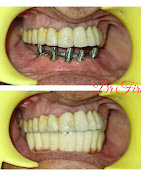

• Dental Implants & Full Mouth Implants: Permanent solutions for missing teeth, including advanced Zygomatic Implants for patients with bone loss.

• Zirconium & Ceramic Crowns: Durable and natural-looking caps to restore damaged teeth.

At Firoz Dental, we combine compassion with precision. Whether it's a simple cosmetic fix or a full smile transformation, our patient-centric care ensures safety, comfort, and satisfaction. Visit us and take the first step toward your best smile.